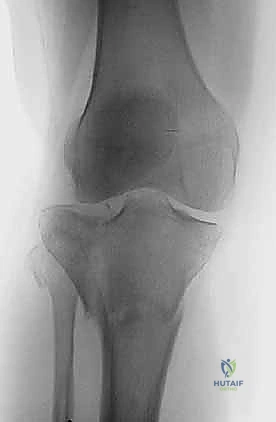

2. التصوير الإشعاعي (X-rays)

الخطوة الأولى هي التقاط صور أشعة سينية من عدة زوايا (أمامية خلفية، وجانبية). تعطي الأشعة السينية فكرة عامة عن وجود الكسر وموقعه، لكنها غير كافية لتقييم الكسور ثنائية اللقمة المعقدة.